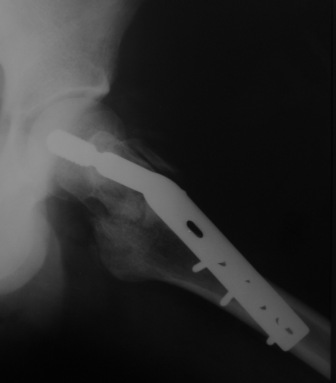

Могу скромно напомнить о существовании стержня нашей модификации.

В частности, на проксимальном конце сделано еще одно дополнительное статическое отверстие. Можно ввести в проксимальном отделе 4 винта, из них 3 статические (2 в круглые отверстия и 1 по нижнему краю овального). Картинки в приложении. На дистальном конце стержня тоже кое-что улучшено. Спрашивайте в аптеках, как говорится. Выпускается предприятием "ЦИТО" (Москва), то есть это малобюджетное решение.

Это было года 2,5 назад, мы тогда еще уточняли возможности шинирования с угловой стабильностью гвоздем с поперечным расположением винтов при переломах проксимального отдела бедра. Пациенту не пришлось приобретать намного более дорогой рекон или проксимальный гвоздь. В приложении еще несколько примеров применения того гвоздя при высоких переломах бедра, в том числе с более латеральной точкой входа. Гвоздь изгибаем для этого.